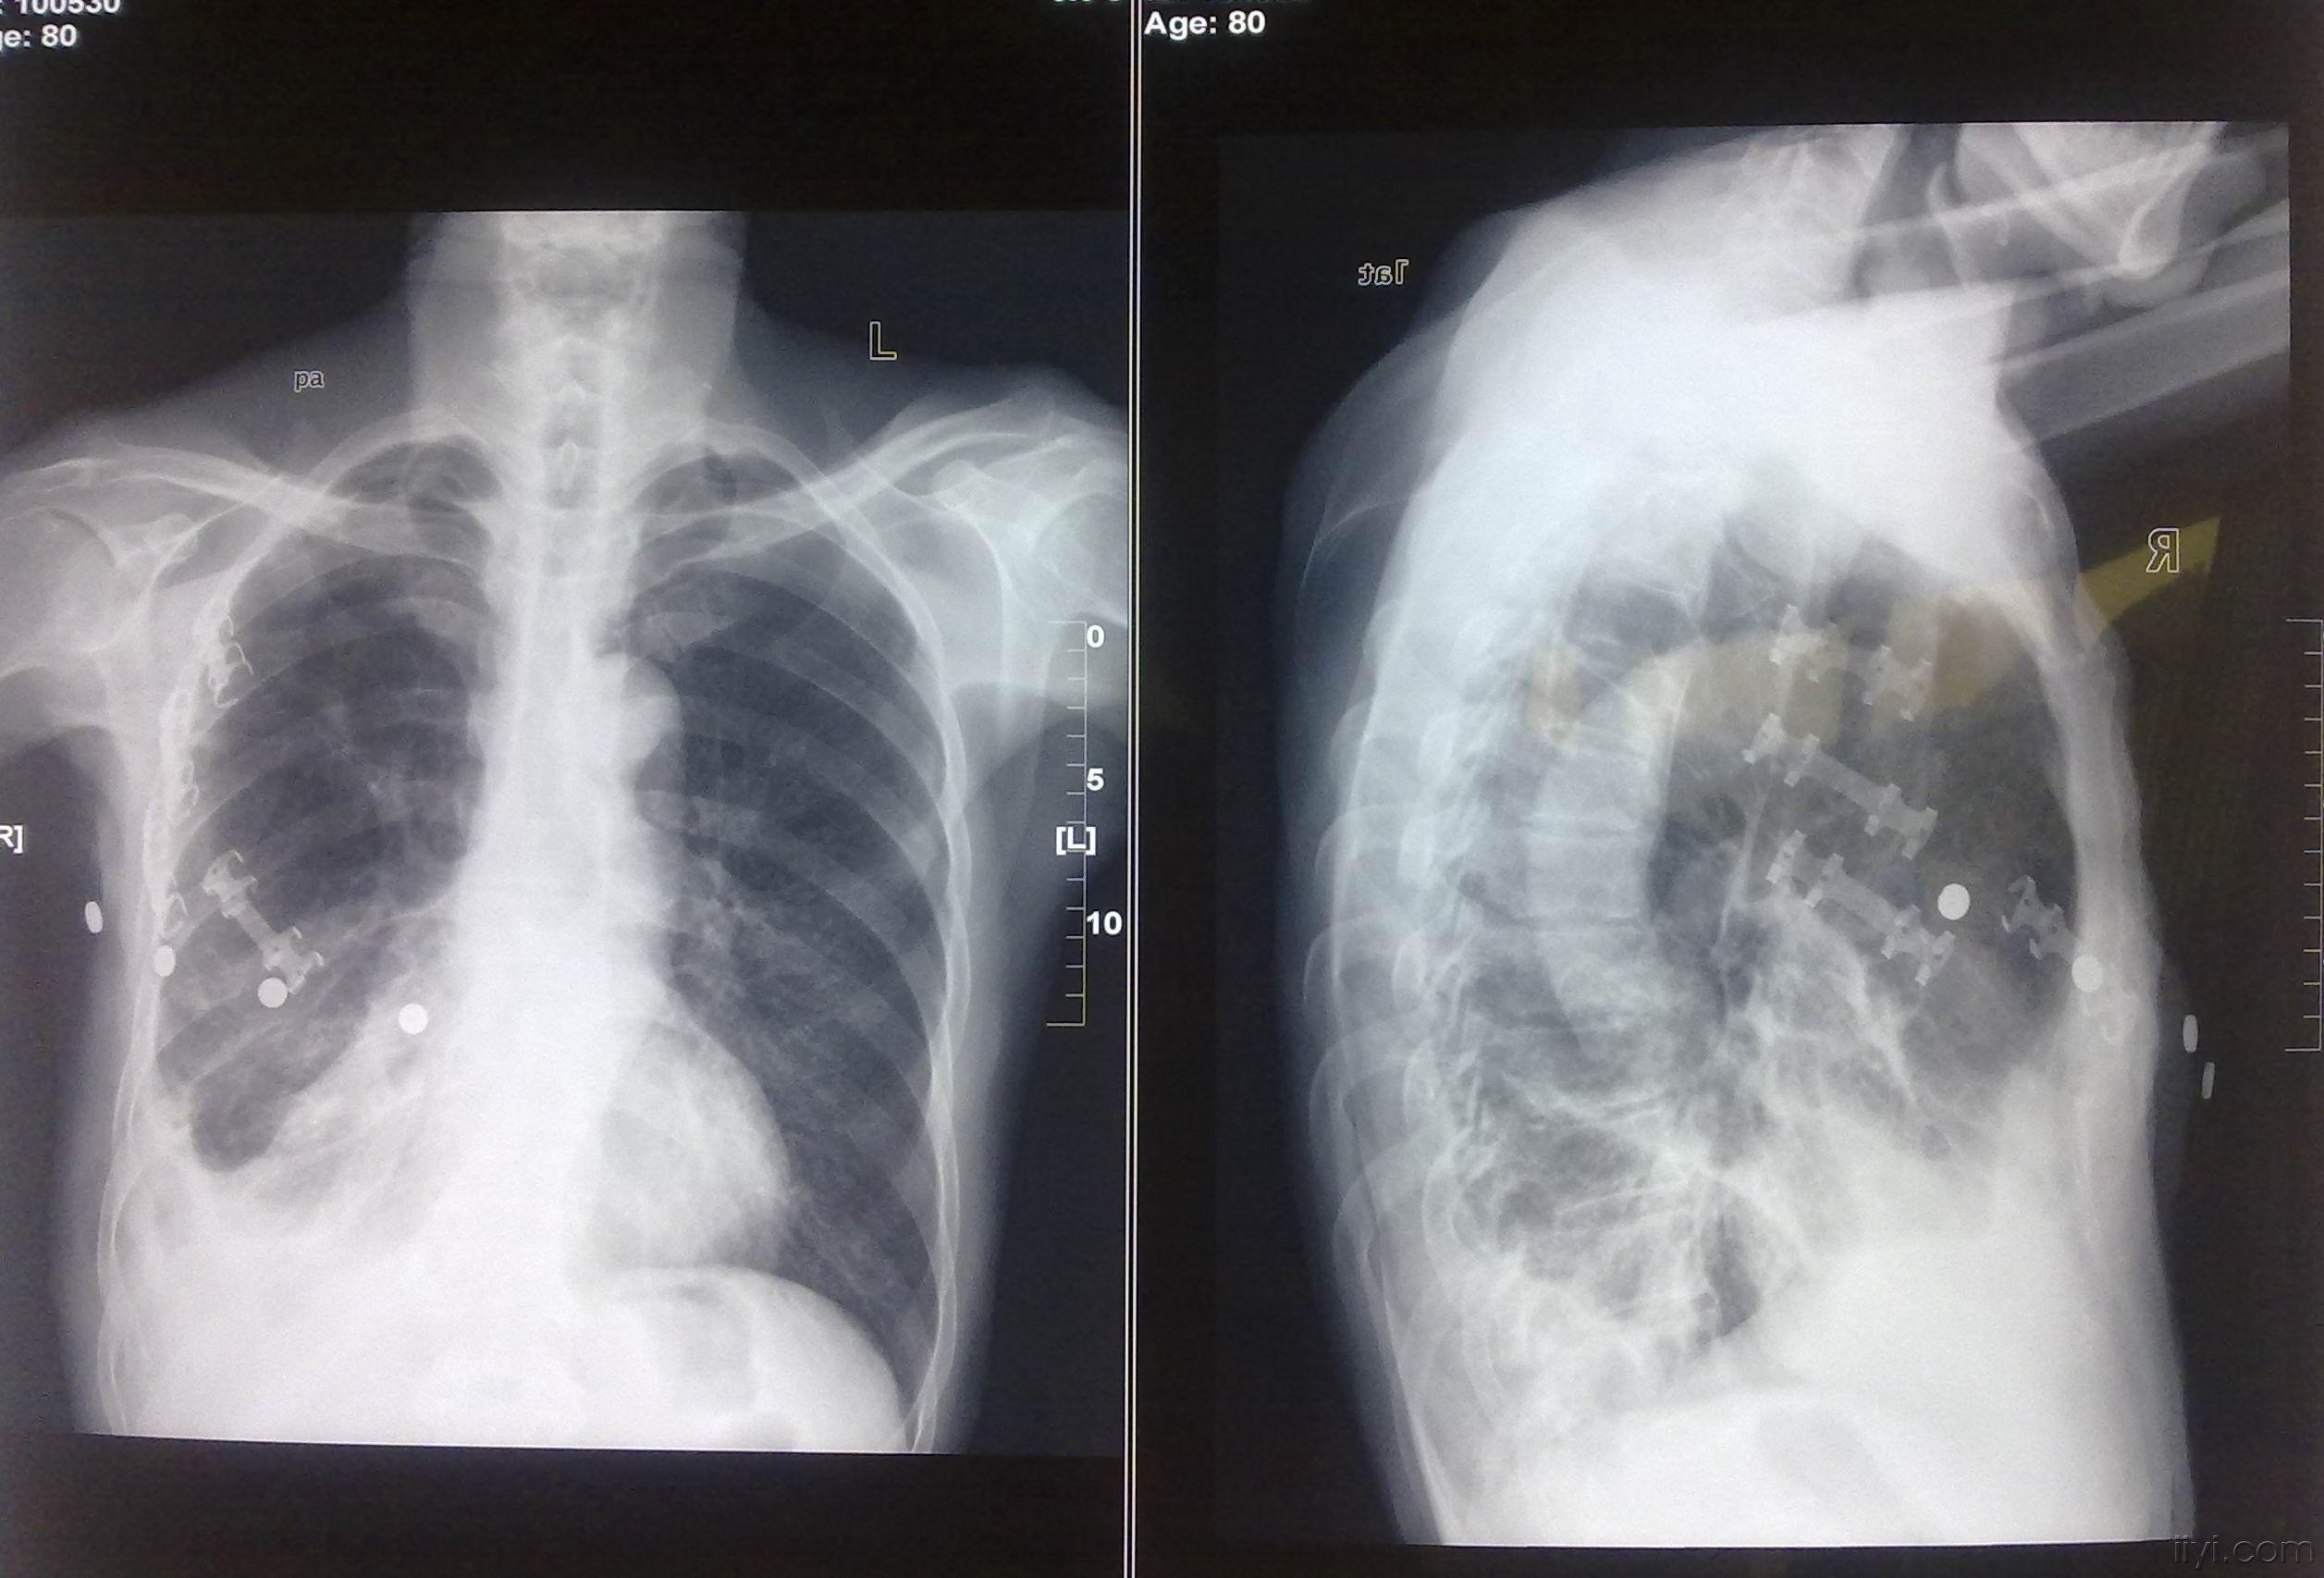

肋骨骨折x光片暴力,肋骨骨折x光片片子

多发性肋骨骨折创伤性湿肺术后肺积血治疗讨论(付经典肋骨重建图片)

肋骨骨折胸片

肋骨骨折x线图片